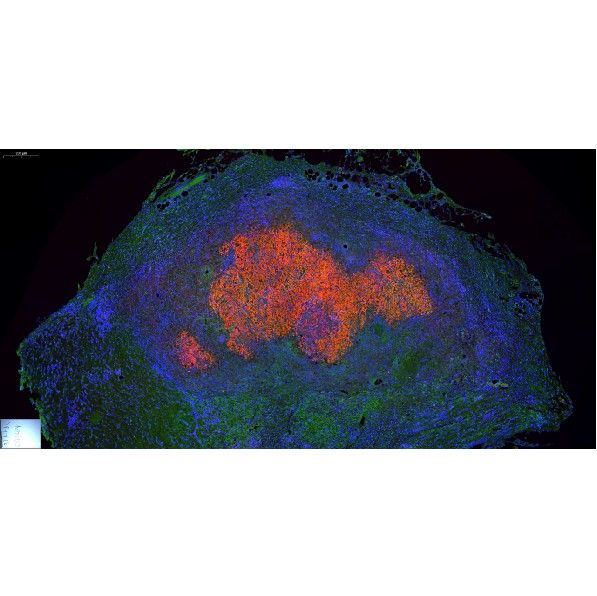

免疫熒光

IF免疫熒光